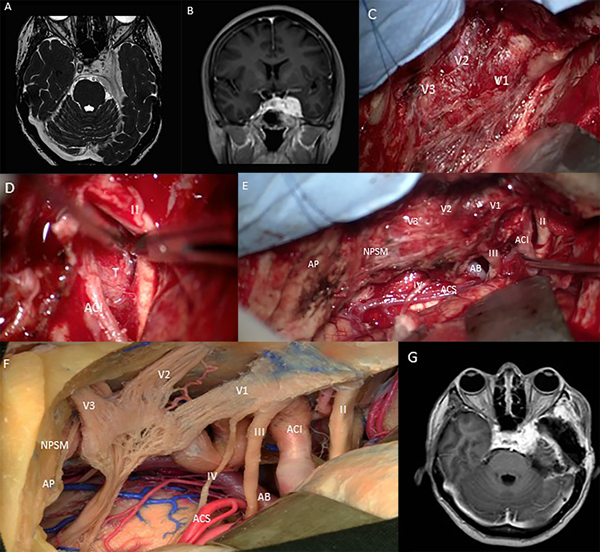

Mujer de 51 años con antecedente de lupus eritematoso sistémico que presentó diplopía de 6 meses de evolución, examen neurológico que reveló hipoestesia facial izquierda en los dermatomas oftálmico y maxilar, parálisis incompleta del III par y del VI par. La agudeza visual fue de 20/60. La resonancia magnética de cerebro mostró lesión extra axial en región esfenotentorial izquierda que involucra el seno cavernoso con engrosamiento y estenosis de la ACI cavernosa (Fig. 3 A, B). El paciente fue sometido a un abordaje pretemporal izquierdo con peeling de la fosa media (Fig. 3 C,D) y se logró la resección subtotal del tumor junto con la descompresión del nervio óptico (Fig. 3 E,F). La resonancia magnética postoperatoria mostró una resección subtotal del tumor (Fig. 3 G). Un mes después de la cirugía, la hipoestesia facial izquierda y la diplopía mejoraron con solo debilidad en el músculo recto medial.

FIG 3. Caso 1 Fig. A y B. RM preoperatoria que muestra un meningioma esfenotentorial que compromete el seno cavernoso izquierdo. C. Peeling de la fosa media que expone las ramas del nervio trigémino. D. Después de la extirpación de la apófisis clinoides anterior, acceso al techo del seno cavernoso que muestra el tumor entre el nervio óptico y la ACI cavernosa. E. Panorámica del lecho quirúrgico que muestra el borde libre del tentorio seccionado y se aprecian las estructuras de la fosa media y posterior. F. Espécimen cadavérico que muestra la misma vista que en la vista intraoperatoria en la última imagen. G. Resonancia magnética posoperatoria que muestra la extirpación del tumor que se limita al lateral. AP, Apex Petroso. ACI. Arteria Carótida Interna, tumor T, II Nervio óptico, III Nervio motor ocular común, IV Nervio troclear, AB. Arteria basilar, ACS. Arteria cerebelosa superior, NPSM Nervio petroso superficial mayor.